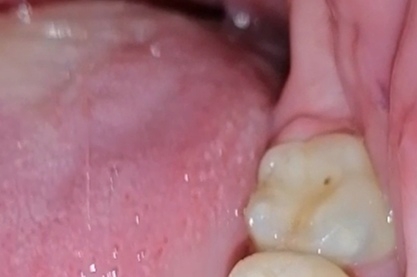

Аноним 04/01/26 Вск 23:32:55 1653988 44

Друзья, спасите, болят вот эти зубы. Указанный стрелкой - депульпированный зуб, лечили каналы, потом перелечивали в декабре, боль не прошла. Иногда не болит в состоянии покоя, а теперь болит. Аж ночью не спалось. Еще заболел зуб после него и почему-то между передними зубами стреляет. На вид ничего нет вроде, ну десна красная и пощипывает. Писал своему врачу, он говорит я в отпуске, когда вернусь не знаю, в той стоматологии больше не работаю. Сказал делать 3д снимок. Запись в частные через 10-14 дней минимум.